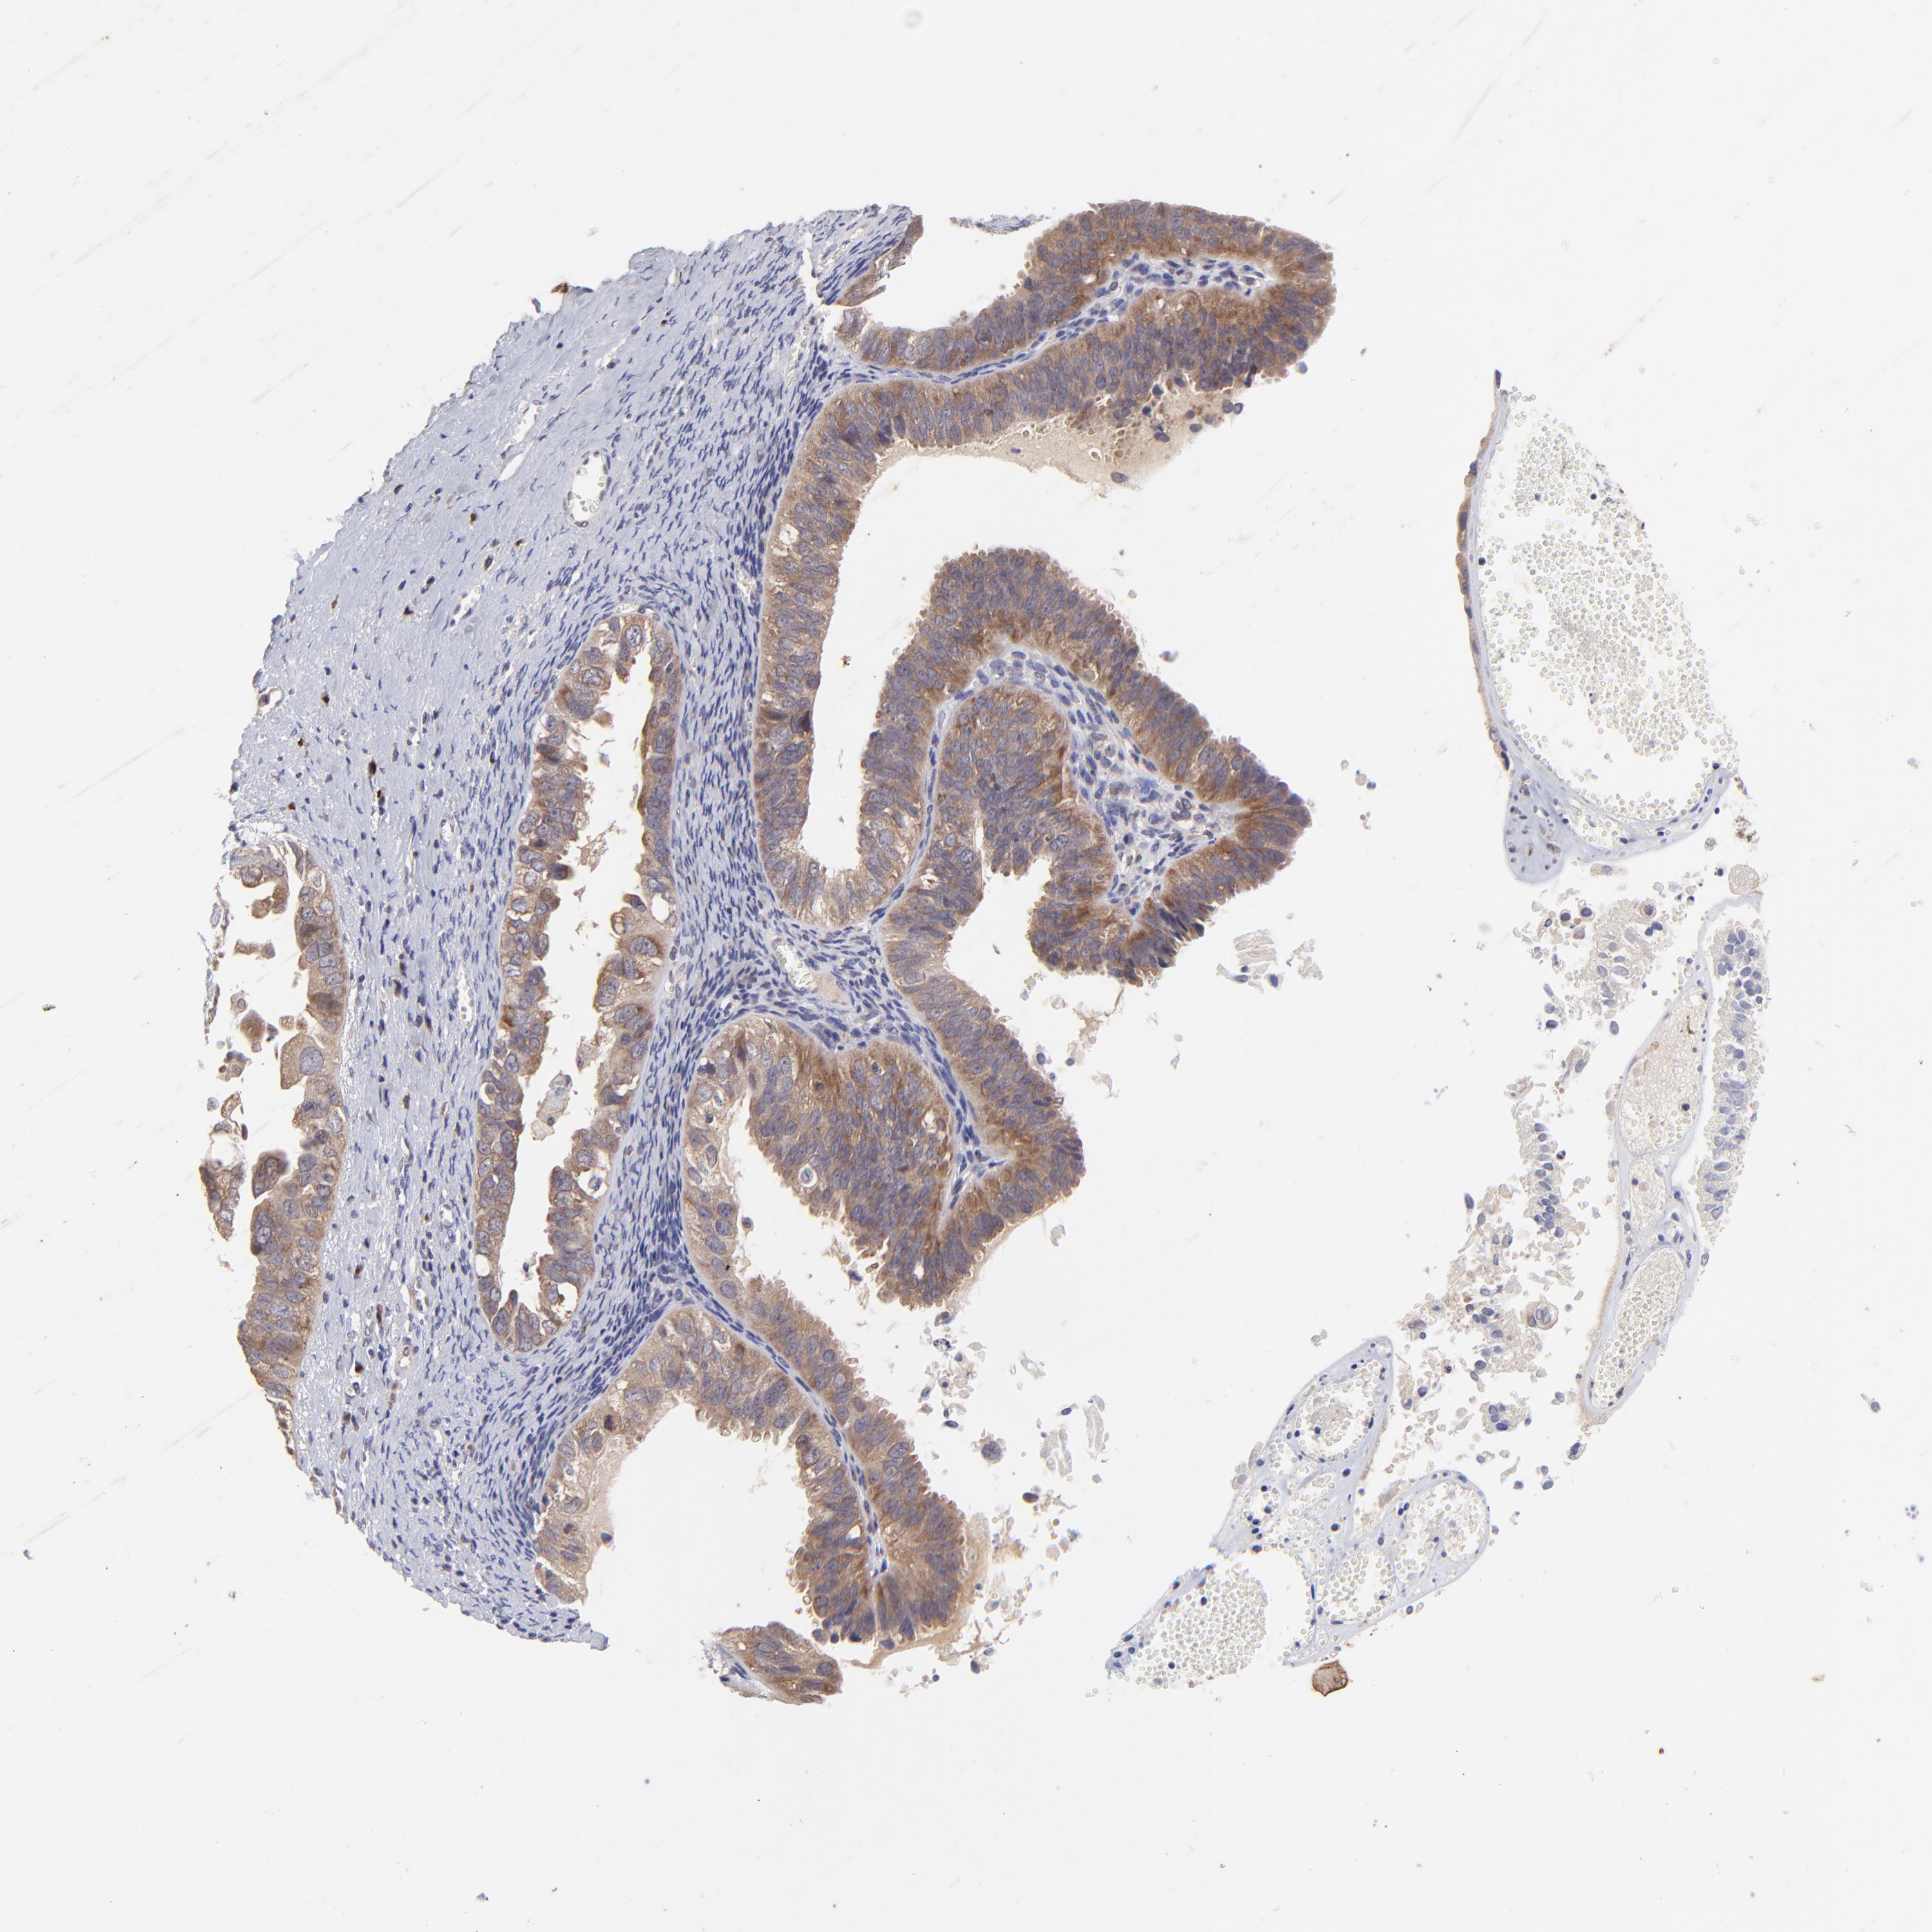

OVARIAN CANCER - Protein expressioni

A mouse-over function shows sample information and annotation data. Click on an image to view it in a full screen mode. Samples can be filtered based on level of antibody staining by selecting one or several of the following categories: high, medium, low and not detected. The assay and annotation is described here.

Note that samples used for immunohistochemistry by the Human Protein Atlas do not correspond to samples in the TCGA dataset.

Antibody stainingi

Antibody staining in the annotated cell types in the current human tissue is reported as not detected, low, medium, or high, based on conventional immunohistochemistry profiling in selected tissues. This score is based on the combination of the staining intensity and fraction of stained cells.

Each image is clickable and will lead to virtual microscopy that enables deeper exploration of all samples and also displays staining intensity scores, fraction scores and subcellular localization as well as patient and tissue information for each sample.

Antibody HPA003180

Staining

High

Medium

Low

Not detected

Intensity

Strong

Moderate

Weak

Negative

Quantity

>75%

75%-25%

<25%

None

Location

Nuclear

Cytoplasmic/membranous

Cytoplasmic/membranous,nuclear

Carcinoma, endometroid

Cystadenocarcinoma, serous, NOS

Cystadenocarcinoma, mucinous, NOS